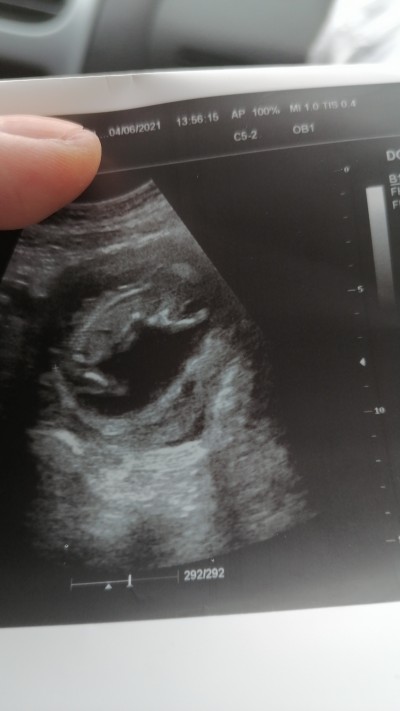

Doktorum kesin bırsey demedi de cevrem dekiler duruşuna göre  beden yapısına gore belli olur demıslerdı ne kadar da dogru bilmiyorum bakabilır mısınız acaba rica etsem

Gebelik haftası 15

Kapatılma nedeni: Cinsiyet tahminlerini sol üst köşeden konu dışı sohbetten sorabilirsiniz